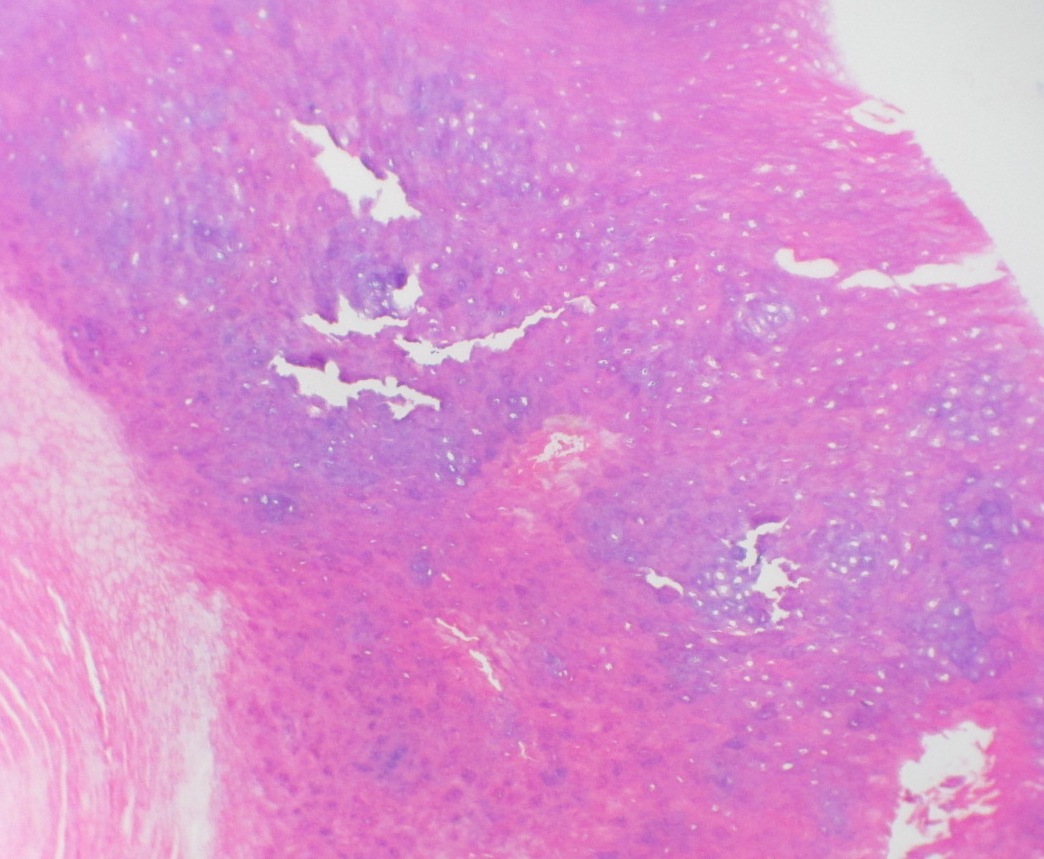

Relatamos um caso de mulher, 51 anos, com história de longa duração de alterações no aspecto da unha do hálux esquerdo e dor local intensa. Após diversos tratamentos, já com o diagnóstico de verruga subungueal, foi suspeitada a existência de tumor glômico pela história clínica e testes semiológicos sugestivos. Foi realizada cirurgia, com a confirmação histopatológica das duas hipóteses.

O possível diagnóstico é a soma de história clínica sugestiva, testes ambulatoriais e exames de imagem, contudo somente confirmado pela histopatologia.

O tratamento é cirúrgico, tratando a dor e evitando a recorrência. O presente caso relata associação de diagnósticos (tumor glômico e verruga subungueal) culminando com as importantes alterações no aspecto da unha.